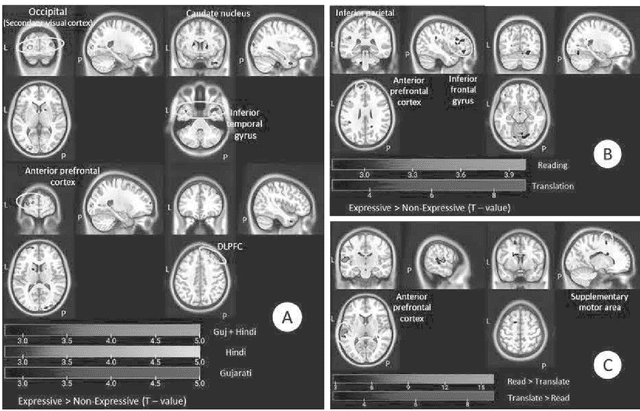

Abstract:Speakers of all human languages make use of grammatical devices to express attributional qualities, feelings, and opinions as well as to provide meta-commentary on topics in discourse. In general, linguists refer to this category as 'expressives'in spite of the fact that defining exactly what 'expressives' are remains elusive. The elusiveness of expressives has given rise to considerable speculation about the nature of expressivity as a linguistic principle. Specifically, several scholars have pointed out the 'special' or 'unusual' nature of expressives vis-a-vis 'normal' or 'natural' morpho-syntax.